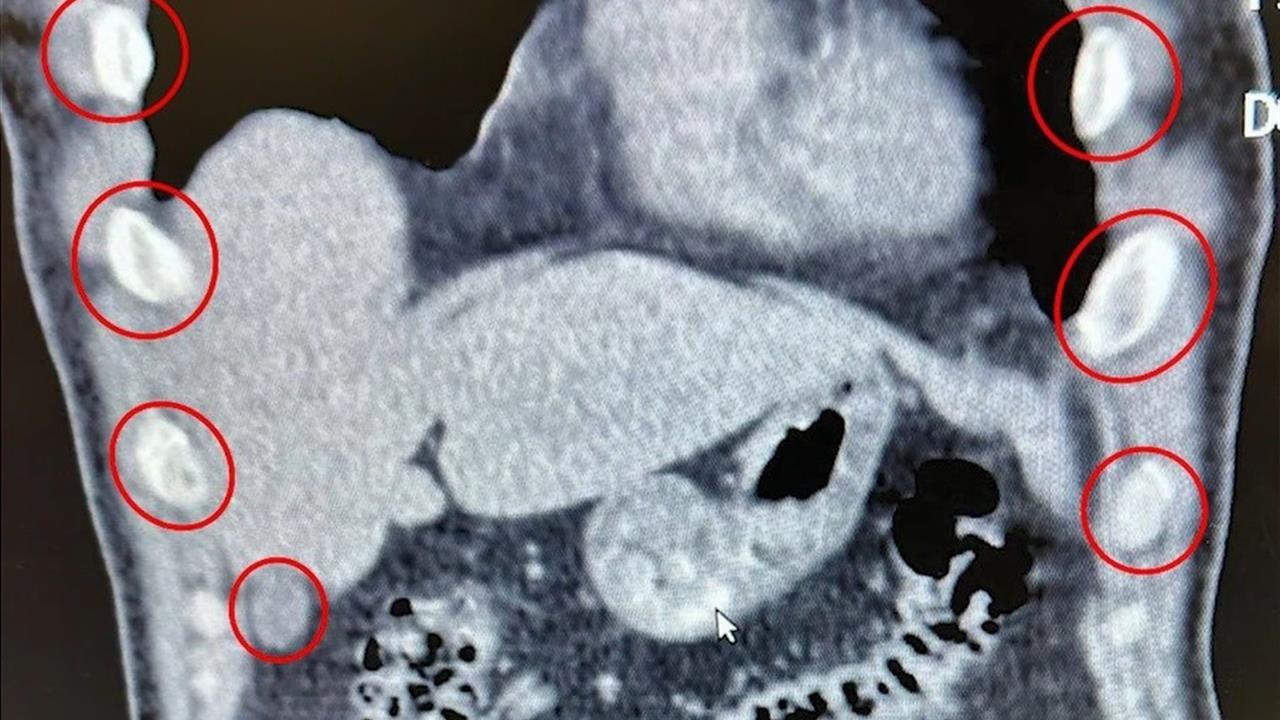

Bitlis İl Emniyet Müdürlüğü Narkotik Suçlarla Mücadele Şube Müdürlüğü ekipleri, uyuşturucu ile mücadele kapsamında önemli bir operasyona imza attı. Tatvan ilçesinde bir otobüste yolcu olarak seyahat eden iki yabancı uyruklu şahıs durduruldu ve gözaltına alındı. Yapılan tıbbi müdahale sonucunda, şüphelilerin midelerinden 136 kapsül halinde toplam 1 kilo 48 gram metamfetamin çıkarıldı.